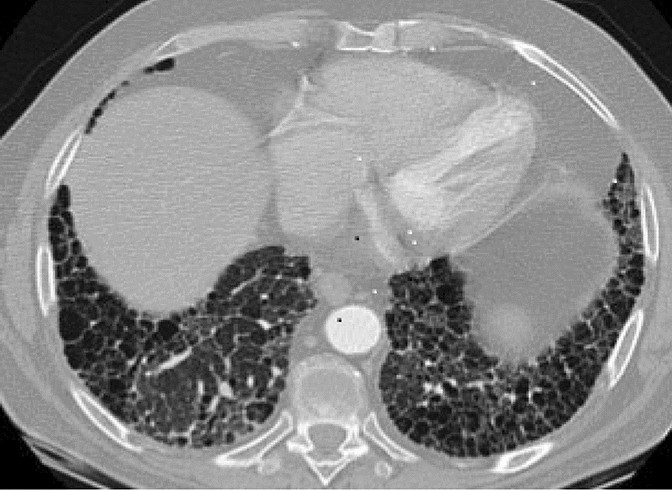

MTX-induced pneumonitis (MTXip) is an acute inflammatory pulmonary complication. It is uncommon and reported to occur in 1% of RA patients commencing MTX [6]. It is associated with non-specific clinical features such as fever, shortness of breath, dry cough, hypoxia and negative cultures. Onset is usually within less than 12 months of MTX start-up [7]. Diagnosis of MTXip can be difficult due to its non-specific presentation. Several authors have proposed criteria to help confirm the diagnosis—Carson and Searles and Mckendry [8, 9]. HRCT changes include diffuse, bilateral ground glass change. (Fig. 1).

Transverse computed tomography (CT) image of chest showing diffuse ground glass inflammatory change in a case of MTXip in a patient with rheumatoid arthritis. Black areas are unaffected lung. There was no zonal predilection